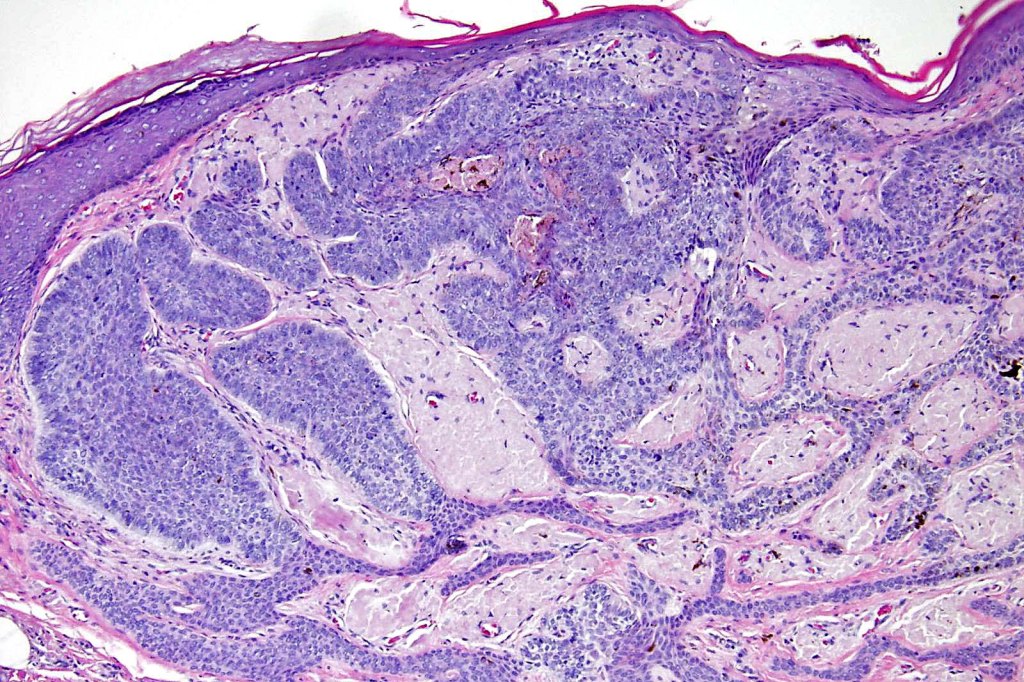

•Multifocal origin from epidermis

•Anastomosing basaloid, narrow epithelial strands associated with a prominent fibrous (sometimes myxoid) stroma

•Peripheral palisade

•Retraction artifact variably present